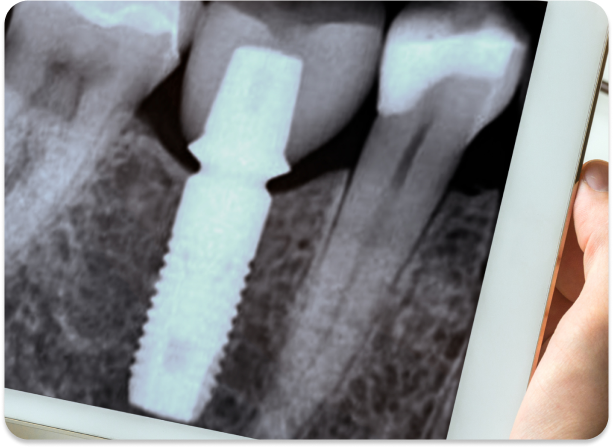

Zirconium implants are a safe alternative with the best osseointegration rate on the market.

Our metal-free implants made with state-of-the-art monolithic zirconium offer a more compatible alternative for your body. These implants represent the latest technology in holistic dentistry.